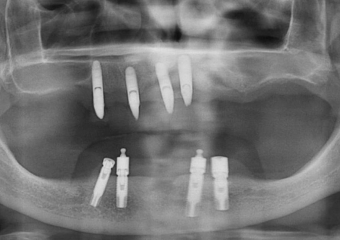

Raio X com implantes Cone Morse e próteses fixas em porcelana